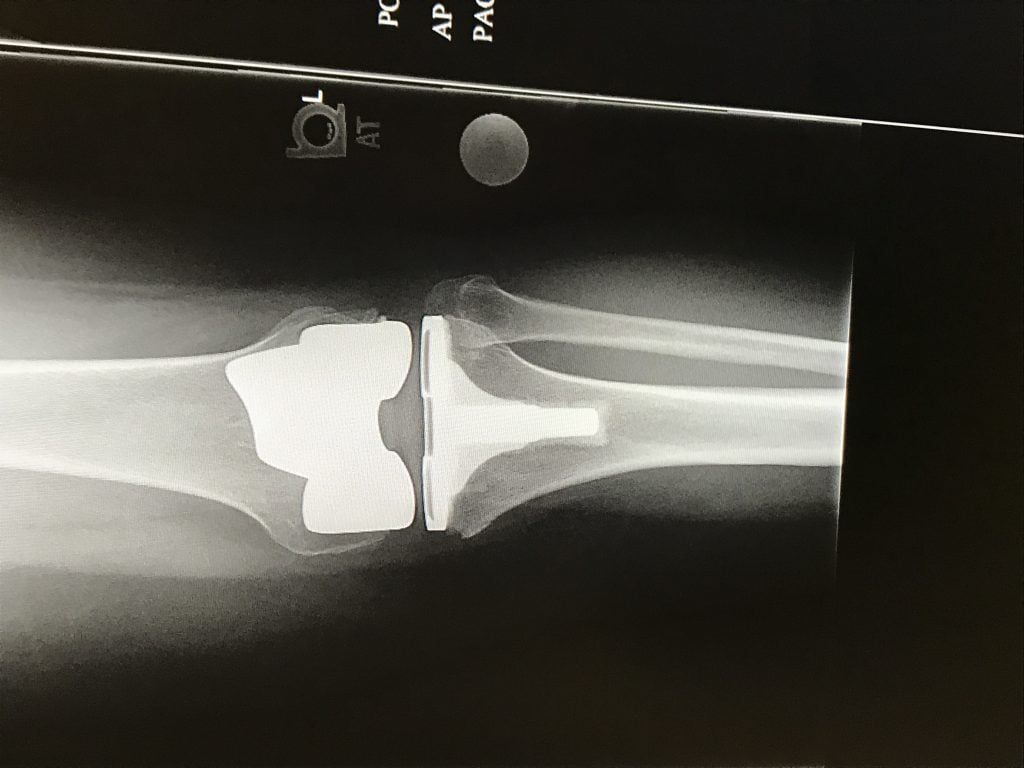

After several years of cortisone and Synvisc shots, I finally went locally to two surgeons to discuss a full knee replacement. In these visits I was turned away, which made me feel very discouraged. I then reached out to our corporate medical doctor who suggested that I see the best orthopedic doctor in the country and that is when I found Dr. Danyal Nawabi! My very fist consultation with him I knew I was in the right place. He was very optimistic and ensured me he could fix this ongoing problem that was affecting my quality of life. He explained in detail why I was in so much pain and told he me that he could fix it! I never thought I would hear those words after being turned down previously. I immediately scheduled my full knee replacement surgery which took place 3 months after my first consultation. The surgery went well and I woke up feeling relieved of all pain. I am now 6 months post operation and feel like a new woman! Every visit with Dr. Nawabi he ensures me that I made the right decision and he extended my life. I am forever grateful. Thank you Dr. Danyal Nawabi!